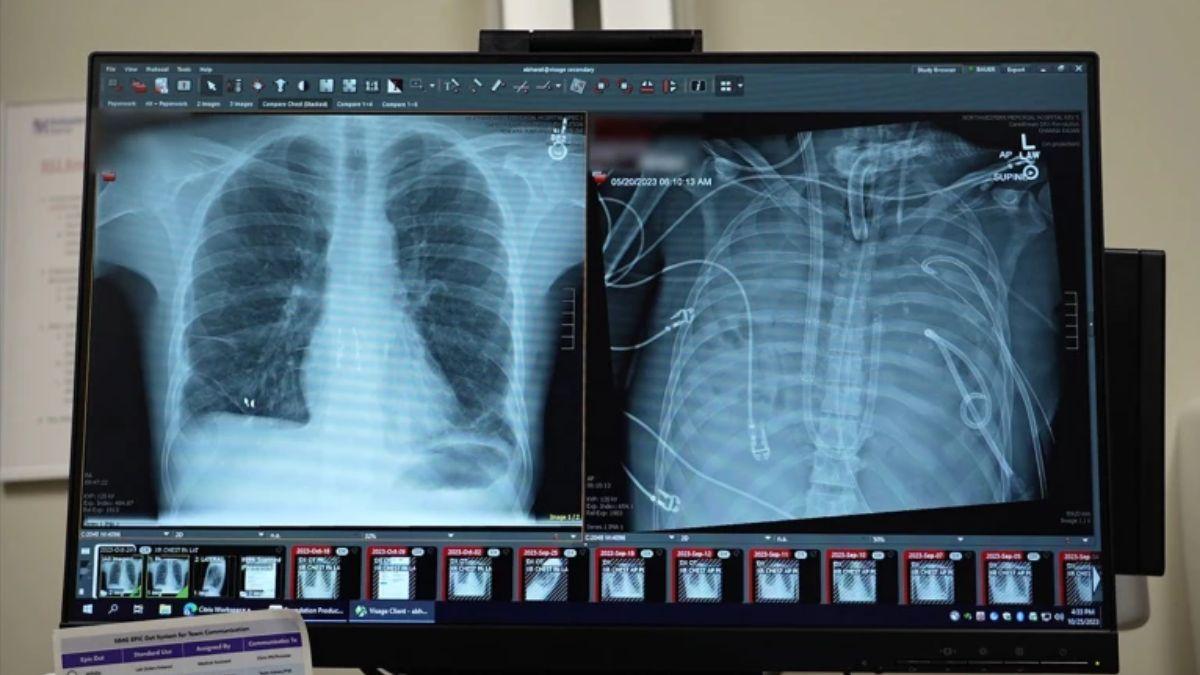

Las radiografías muestran los pulmones nuevos (izquierda) y los pulmones viejos (derecha) del paciente de 33 años que fue intervenido. / Crédito: Northwestern Medicine.

El dispositivo, que destaca por su capacidad para ajustar flujos y preservar un tránsito sanguíneo fisiológico hacia y desde el corazón, hizo posible mantener la hemodinámica mientras el cuerpo del paciente se recuperaba de la infección. Tras la extracción de los pulmones dañados, la presión arterial y la función de órganos se estabilizaron, la carga infecciosa disminuyó y, dos días después, se pudo realizar con éxito un trasplante bilateral de pulmón. Más de dos años después, el paciente ha retomado una vida cotidiana con buena función pulmonar, según los autores.